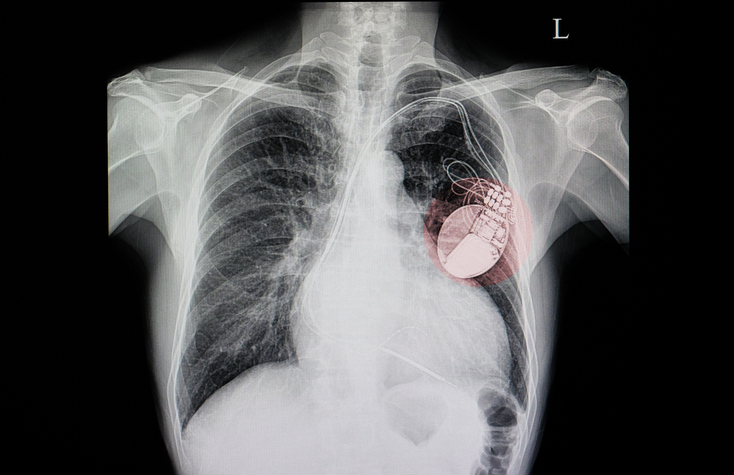

They supplemented the repair work by fixing then new-fangled televisions, reselling medical devices…and custom-building medical devices for area hospitals and doctors. One of those doctors, a University of Minnesota heart surgeon named C. Walton Lillehei asked Bakken in 1958 if it was at all possible to build a battery-powered pacemaker. Up until that time, patients with an irregular heartbeat relied on wall-powered, and very large, pacemakers. Not only did that limit their comings and goings, but if there was a power outage, they might die.

That’s actually what prompted Lillehei’s request — he oversaw pediatric heart patients, and one night a power outage led to a death. Bakken fulfilled the request. Adapting a circuit he found in a magazine, and utilizing batteries and a transistor, Bakken developed the first-ever external, wearable, battery-powered pacemaker. Two years later, Bakken and Medtronic developed the first surgically implantable pacemakers. Those inventions have saved the lives of countless millions, including Bakken — he got his first pacemaker in 2001.